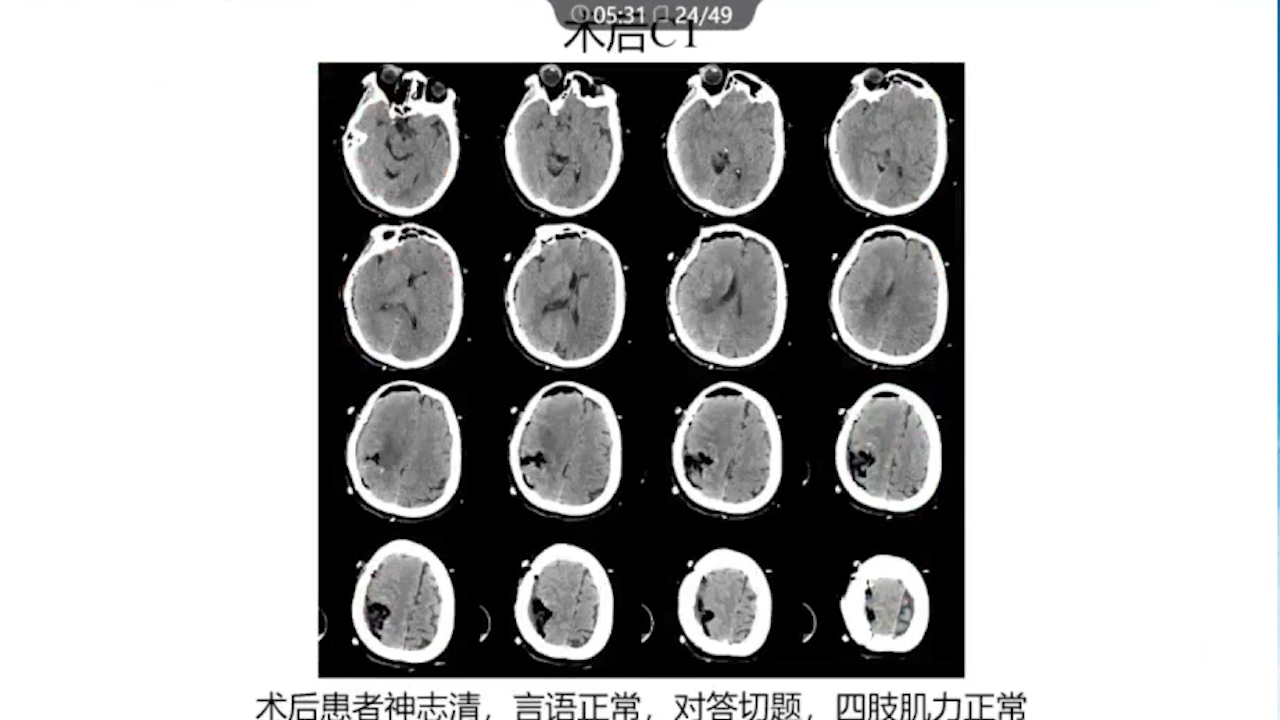

1、术前需要完善的影像学检查、多模态融合及神经导航以进行精确的肿瘤及静脉血管定位。

7、术中辅助技术:实时定位并保护静脉,监测其通畅性(荧光造影、Flow800)。

8、术后积极进行脱水治疗:如果术后脱水不及时,将可能发生严重的脑水肿,导致功能区脑组织受压、静脉回流障碍等一系列的严重反应。